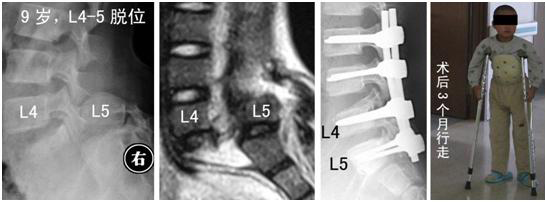

1.女,65岁,肱骨髁间粉碎性骨折,术后肘关节功能大部分恢复

2.前臂双骨折,交锁髓内钉固定

3.桡骨末端掌侧Barton骨折

4.男,35岁,车祸致多发创伤

1)股骨上端骨折

2)胫腓骨下端粉碎性骨折

3)L1、L2骨折

5.女,66岁,外伤致股骨下端骨折,行股骨逆行交锁髓内

钉固定术

6.女,43岁,车祸致胫骨平台骨折

7.男,49岁,胫腓骨骨折,径胫骨髓内钉固定+腓骨钢板固定

8.男,44岁,高处坠落伤致左髋臼、骨盆骨折

9.男,55岁,高处坠落伤致跟骨骨折

10.C6陈旧性骨折脱位